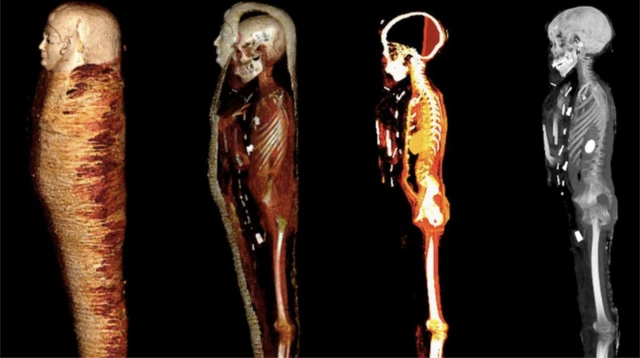

වර්තමානය වන විට, මෘතශරීරවලට හානි කිරීමෙන් තොරව අධ්යයනය කිරීම සඳහා පරිගණකගත ටොමෝග්රැෆි තාක්ෂණය මනා මෙවලමක්ව තිබේ. එමඟින්, "පුරාණ කාලයේ මිනිසුන්ගේ සෞඛ්යය, විශ්වාසයන් සහ හැකියාවන් ගැන වැඩි තොරතුරු" අනාවරණයකර ගැනීමට විද්යාඥයින්ට ඉඩ සලසන බව විශේෂඥයා කියා සිටියේ ය.

"පරිගණකගත ටොමෝග්රැෆි තාක්ෂණය, විකිරණවේදයේ සැලකිය යුතු ප්රගතියක් නියෝජනය කරනවා. තනි තනි පින්තූර පාවිච්චි කරනවා වෙනුවට, සිරුරේ තුනී ඡේදයන් සියගණනක ප්රක්ෂේපණයන් පාවිච්චි කරලා සම්පූර්ණ ත්රිමාණ ආකෘතියක් නිර්මාණය කරන්න පුළුවන්," ඔහු කතාව අවසන් කළේ ය.

'ස්වර්ණමය කොලුවා'ගේ මෘතශරීරය ශෛලමය දෙණ ද්විත්වයකින් ආරක්ෂාකර තිබුණි: ඒවායේ පිටත ග්රීක භාෂාවෙන් සටහන් තබා තිබූ අතර අභ්යන්තරය දැවයෙන් නිමකරවා තිබුණි. මෘතශරීරය රන් වෙස් මුහුණක් පැළඳ සිටියේ ය.